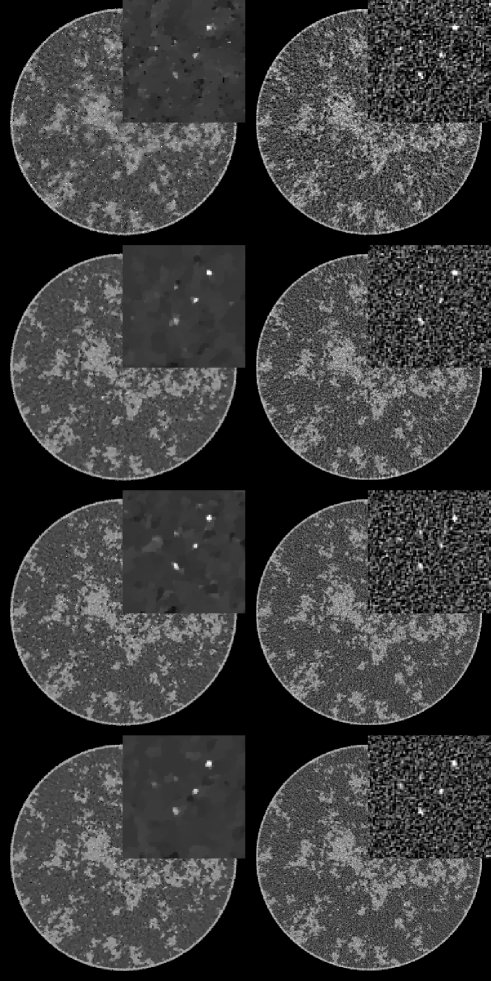

For this initial survey of a breast CT simulation, we show two main sets of results. The first set of images are reconstructed from noiseless data for different numbers of views. The idea is to see how well TV-minimization performs in recovering the complex breast phantom under ideal conditions. The second set of images includes noise at a fixed exposure, and as described in Sec. II-B, the noise-level per projection increases with the the number of projections.

IV-B image reconstruction from noisy data

For the noise studies, we again investigate data sets with the view number varying between 64 and 512. For these reconstructions, is also varied between and . In Fig. 3, we show the TV-minimization images compared with FBP, as a reference. The optimal values of for each TV-minimization image is chosen by visual inspection. The FBP fill images are smoothed by convolving with a Gaussian distribution of width 140 microns (chosen by visual inspection), and the ROI images are unregularized. While it is not too surprising that the FBP image quality appears to increase with projection number, it is somewhat surprising that the same trend is apparent for image reconstruction by TV-minimization. The 512-view data set seems to yield, visually, the optimal result in that the ROI appears to have the least amount of artifacts. While most of the micro-calcifications are visible in each reconstruction, the artifacts and noise texture in the sparse-view images can be distracting and mistaken for additional micro-calcifications. It seems that the increased noise-level per view impacts the reconstruction less than artifacts due to insufficient sampling. That we obtain this result with a CS algorithm is interesting, and warrants further investigation with more rigorous and quantitative evaluation.